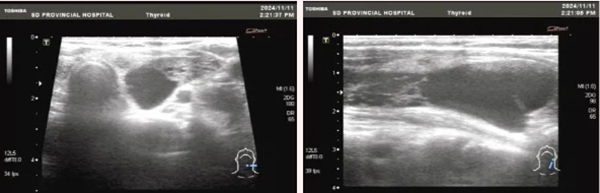

73岁的王某是济宁人,1个多月因冠心病就诊当地医院心内科行冠状动脉支架置入术。因病变广泛且复杂,尚有3处病变未处理,拟择期再次行冠脉支架置入术。但复查期间发现患者血钙升高,血生化示血钙3.6mmol/L(参考范围2.2-2.7)。进一步检查血钙升高的原因,发现患者甲状旁腺素明显升高达到600pg/ml(参考范围15-65)。甲状腺及甲状旁腺超声提示甲状腺左叶后方包块,大小约7.2*3.9*1.9cm。甲状旁腺核素显像提示甲状腺左叶背侧肿块放射性增高。当地医院诊断为甲状旁腺功能亢进症、甲状旁腺腺瘤。心内科考虑患者围手术期风险较高,建议患者先治疗甲旁亢,待血钙稳定后再处理冠脉病变。

入院后,景斐副主任医师带领团队对患者的病情进行了全面评估,完善术前准备后,为患者进行了超声引导下经皮甲状旁腺微波消融术。整个治疗过程只需局部麻醉,30分钟就完成了治疗。治疗后,患者颈部只留下针眼大小的伤口,无局部不适及声音嘶哑等。术后,患者复查甲状旁腺素降至68pg/ml,血钙也逐渐降至正常,停用了所有降钙药物。患者乏力、精神欠佳的症状也逐渐好转。